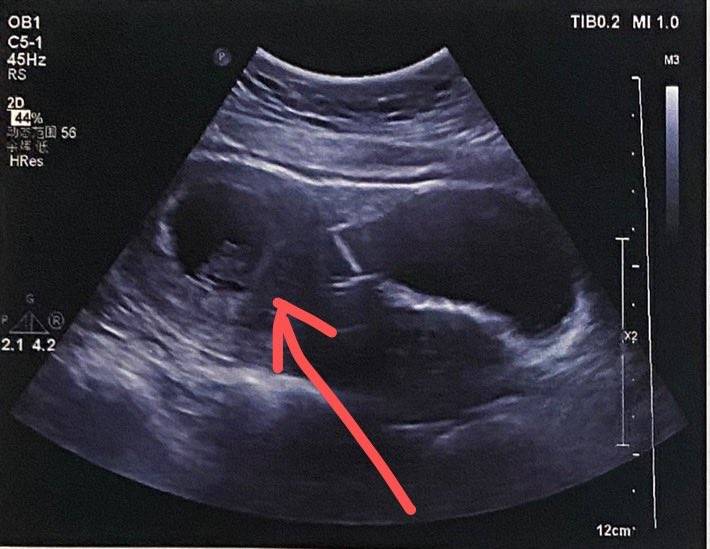

再做个阴超(简直羞耻➕痛苦)

结论:偏小一周!

后来说子宫动脉高,要打间苯三酚,好!打……